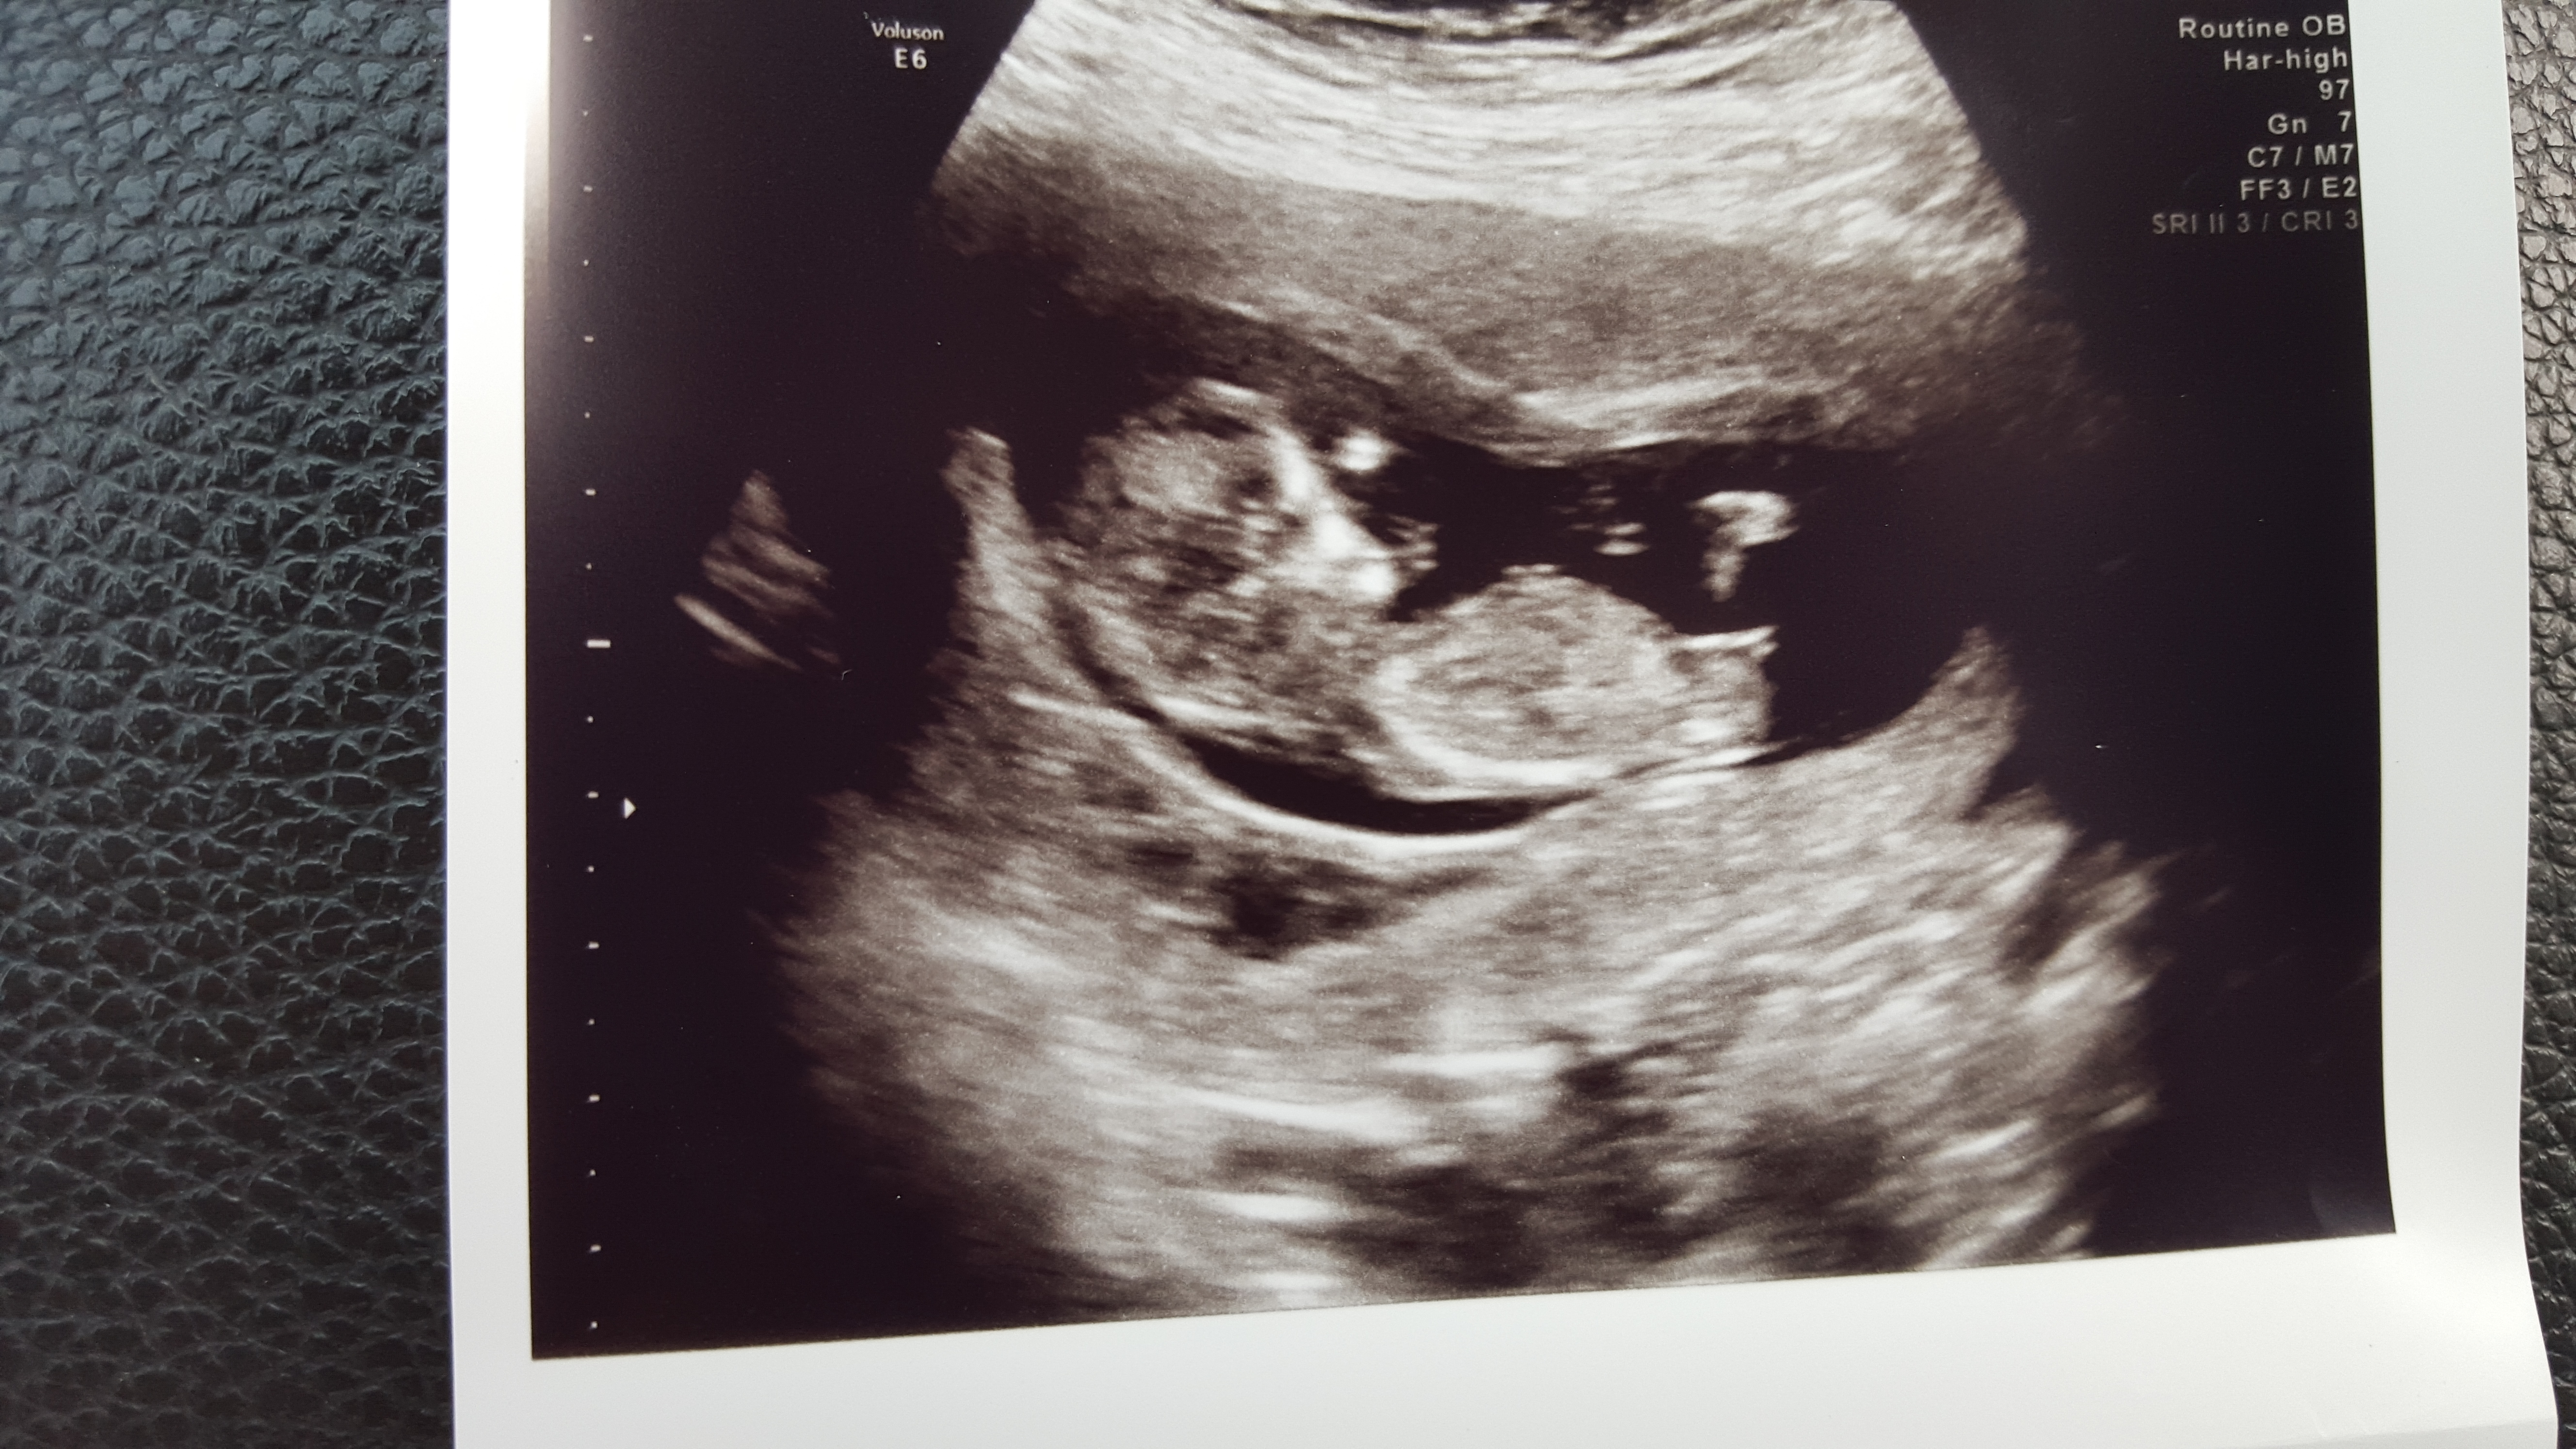

12 weeks 1 day Attachment 25940

Looks like a girl.

Girly but early, so nub could still rise.